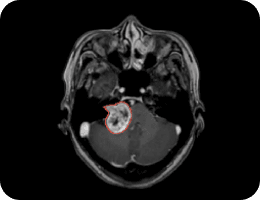

TSHA Project (FEMH)

Meningioma

Neuroma

Stroke Project (CGMH-Kaohsiung)

NCCT Stroke Region

Aiding Lesion Identification

During medical procedures that depend on imaging support, FedMed.tw precisely aids doctors in identifying the location of lesions or organs on images, thereby supporting their treatment efforts.